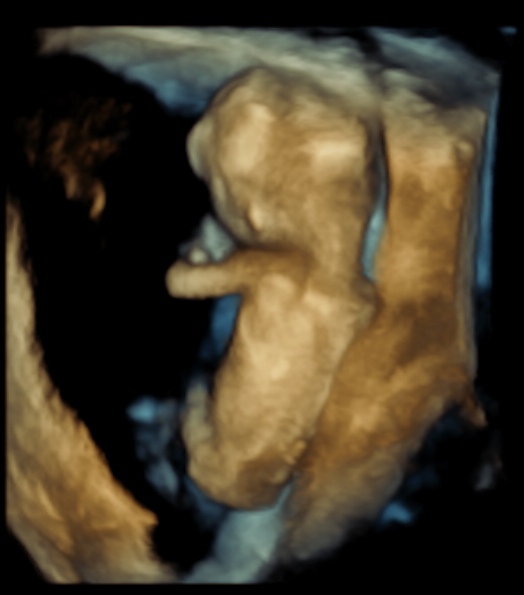

First Trimster Screening (Nuchal translucency, Nasal bone, etc)

This scan is carried out from 11 weeks to 13 weeks and 6 days. The scan is usually performed transabdominally but in a few cases it may be necessary to do the examination transvaginally.